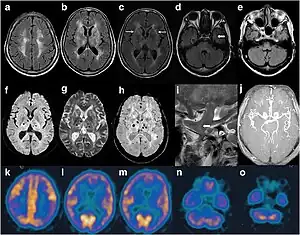

Por si só, a presença de príons causa uso atenuado de glicose pelo tálamo e hipo-metabolismo moderado do córtex cingulado. A extensão desse sintoma varia entre duas versões da doença, sendo aquelas que apresentam homozigotos de metionina no códon 129 e heterozigotos de metionina/valina sendo os mais graves no último. Uma vez havendo relação entre o envolvimento do tálamo na regulação do sono e consciência, uma ligação é banalmente conchavada, sendo, portanto, frequentemente identificada como a causa.[14]

O diagnóstico é hasteado com circunstâncias sintomáticas. Trabalhos peremptórios, vulgarmente executados para primar-se a condição de modo definitivo, incluem estudos do sono e exames de tomografia por emissão de positrões, a PET.[1]

Em 2011, o primeiro caso relatado na Holanda foi de um homem de 57 anos de descendência egípcia. O homem ingressou na sintomatologia com visão dupla e perda progressiva de memória. Sua família também notou que ele tornara-se desorientado, paranoico e confuso. Enquanto adormecia durante atividades diárias aleatórias, ele sofria sonhos vívidos e movimentos musculares indiscriminados durante o sono normal, em ondas lentas. Após 4 meses desde a acepção aos sintomas, passou a ter convulsões nas mãos, tronco e membros inferiores enquanto acordado. A pessoa morreu aos 58 anos, 7 meses após o início dos sintomas. Uma autópsia revelou moderada atrofia do córtex frontal e moderada atrofia do tálamo. Este último é um dos sinais mais comuns da IFF.[20]